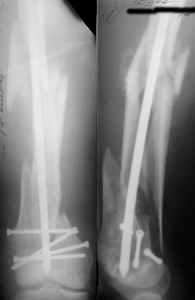

I presented a series of ~25 such cases at EuroTrauma'2004. Many cases were discussed here. I attach am example. Look also recent cases at http://www.hwbf.org/hwb/conf/alex58/scfx.htm,

http://www.hwbf.org/hwb/conf/alex63/alex63.htm

- Your last posted case: how is possible to have secure fixation with applied construct without additional casting, bracing or Ilizarov?

At that moment we had in stock only the 10 mm solid nails so of course there was no idea about early weight bearing. But it was quite enough for early knee ROM excersises (see attached). Two locking screws through the distal block provided that.